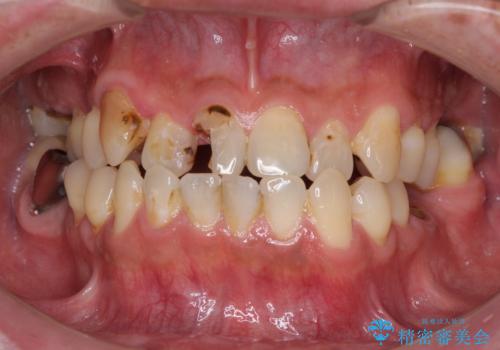

- 前歯や奥歯の虫歯を放置しており、それらの治療を契機に真っ白な歯にしたいとのことで来院された患者様です。

咬み合わせを改善するに当たって、抜歯しなければならない歯や歯列の改善が必要な箇所があったため、矯正治療やインプラント治療から始めていくこととしました。

不自然なくらい真っ白にしたいとのことでしたので、透明感のないフルジルコニアクラウンを用いて補綴することとしました。